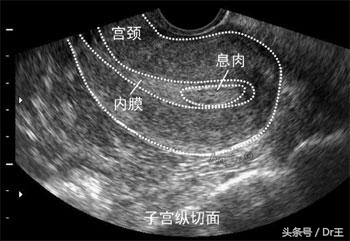

慢性子宫内膜发炎很少有明显的症状,偶尔顶多来个腹痛腹胀或白带多或不正常出血,不过那时大家都会想是骨盆腔发炎或阴道炎等等,很少会直接想到是内膜发炎,若真的是内膜发炎,也不认为它是大病,服服药就可以过关。又加上内膜是在子宫内,所以不易发现它的异常,更增加大家的轻忽,这里要强调的就是单靠超声波,不管阴式或腹式,来诊断是很不准确的。

要诊断是否有内膜发炎有两个方法,一个是作括除手术,看内膜有没有发炎细胞(plasma cell)准确性很高,但说到括除,太麻烦了,病人也会怕,所以目前建议作软式子宫镜检查,它很简单,不用上麻醉,快的话,10分钟内就可完成检查,准确度可达,但这要靠医师的经验。以前不孕医生都在失败后才要求作这一项检查,现在则建议提早作,我也是这样认为,一切检查都稿定了才上路比较是对的作法。

很多女性都认为输卵管摄影就足以诊断子宫腔是否正常,其实这是错的,要了解子宫腔,非作软式子宫镜不可。